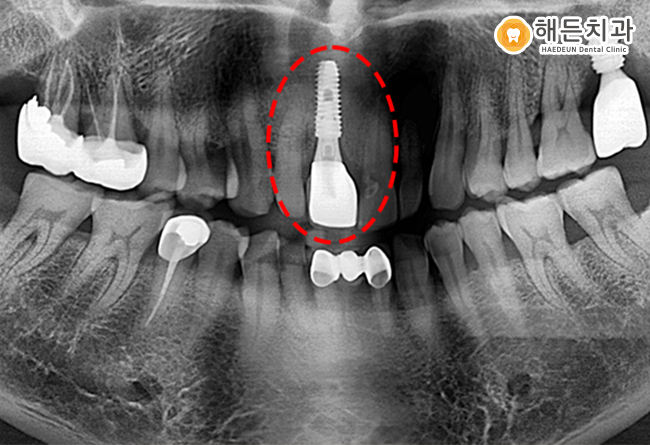

잇몸 염증으로 인해 치조골이 녹아 뼈이식을 진행하고 임플란트를 식립을 진행하게 되었습니다.

발치 후 한 달 정도 잇몸상태를 확인하였고, 잇몸상태가 좋아져 당일 뼈이식과 식립이 동시에 가능하여 함께 이루어졌습니다.

치아의 뿌리 역할을 하는 인공치근은 골 융합도가 높은 티타늄 소재로 제작되었기 때문에

문제없이 환자분의 잇몸뼈와 잘 융합되었습니다.

또한 주위의 자연치아와 유사한 색상의 보철물까지 만족하며 마무리가 되었습니다.